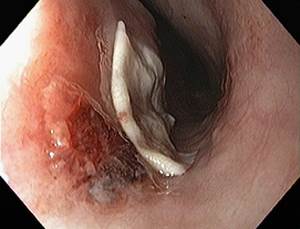

Эндоскопическое исследование позволяет не только обнаружить инородное тело в пищеводе, но и, чаще всего, сразу извлечь его, а также оценить состояние тканей пищевода.

Если это возможно и безопасно, лучше всего удалять инородные тела из пищевода при помощи эндоскопа. Крупные инородные тела, которые невозможно извлечь эндоскопом, проталкиваются в полость желудка и извлекаются при проведении гастротомии (полостная операция с рассечением и последующим ушиванием стенки желудка).